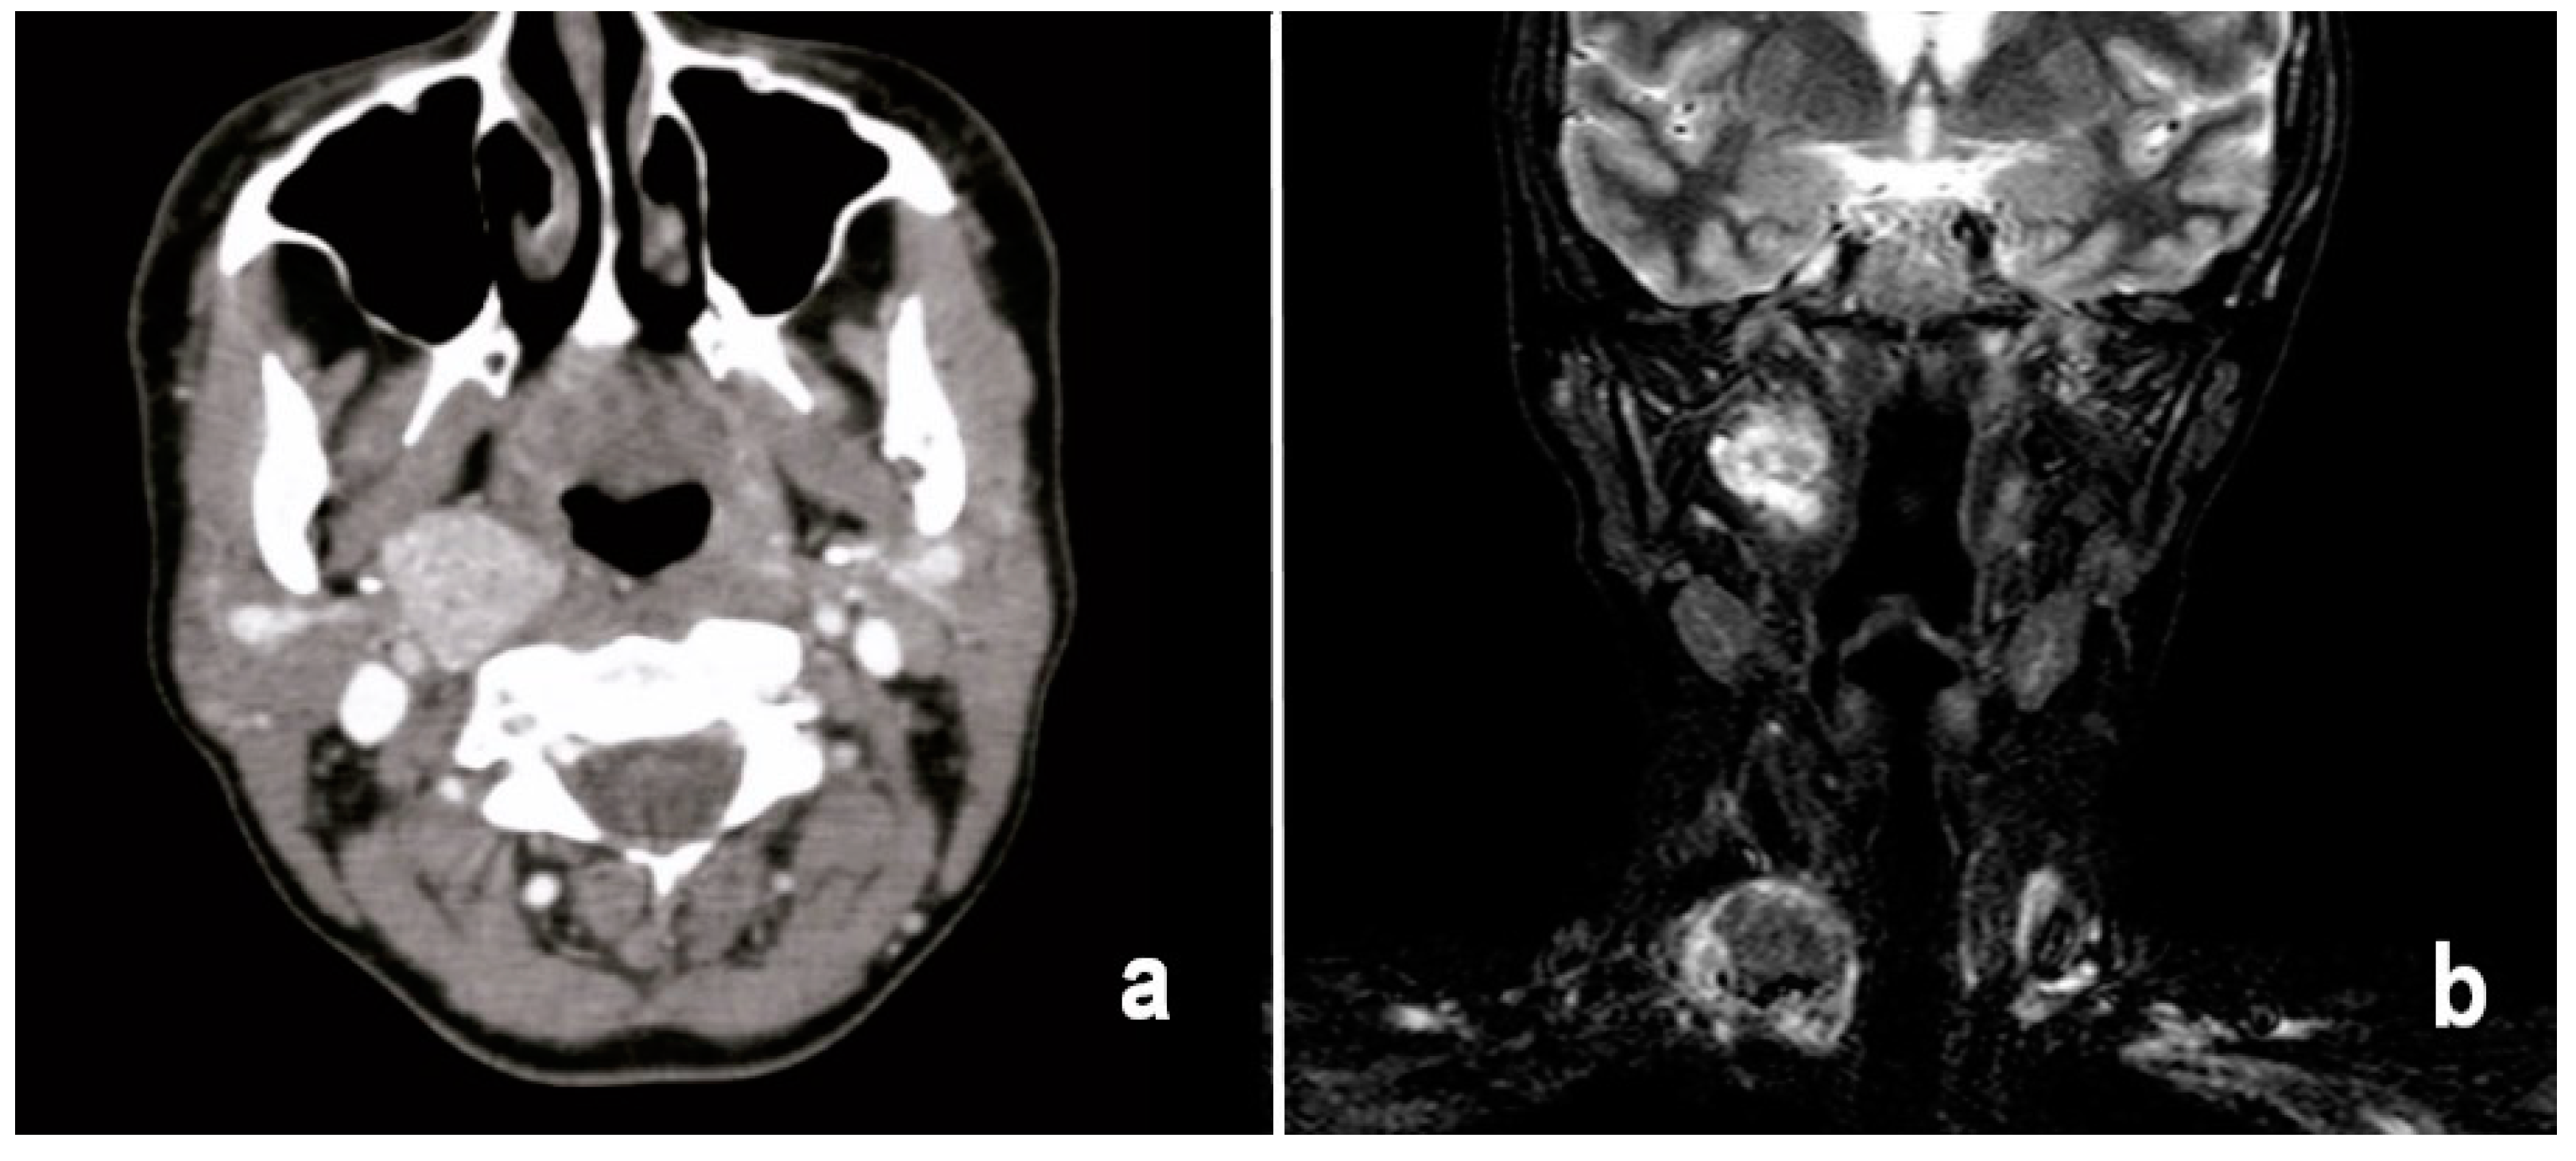

In order to complete the study of the PS mass, computed tomography with contrast and magnetic resonance with contrast were performed.

Both computed tomography and magnetic resonance imaging revealed the presence of a right thyroid node with a diameter of 4.5 × 3.8 cm characterized by a central necrotic–hemorrhagic nucleus, as well as the presence of a right parapharyngeal mass with a diameter of 3.8 × 3 cm (Figure 2).

Figure 2.

(a) Axial CT scan of the parapharyngeal node; (b) coronal MRI scan showing thyroid mass and parapharyngeal metastatic node.